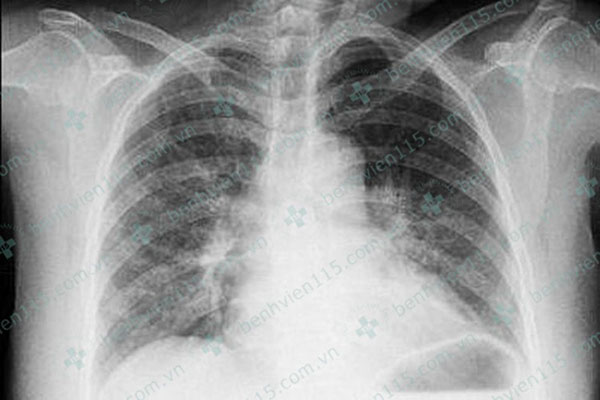

Nhập khoa Tim mạch Tổng quát, Bệnh viện Nhân dân 115, các bác sĩ tiến hành thăm khám và nhận định bệnh nhân không có tiền căn bệnh lý tim mạch, không yếu tố nguy cơ tim mạch cũng như gia đình không có tiền sử mắc bệnh tim mạch sớm. Bệnh nhân vẫn tỉnh táo dù tình trạng đau ngực nhiều kèm khó thở. Khi siêu âm tim phát hiện giãn thất trái.

Ngày đầu nhập viện, bà B. có tình trạng suy tim cấp, phổi ran ẩm 2 phế (phế quản 2 bên phát ra âm thanh bất thường do bị co thắt, chèn ép) trường được xử trí theo phác đồ nhồi máu cơ tim cấp với thuốc đặc trị theo phác đồ nhồi máu cơ tim.